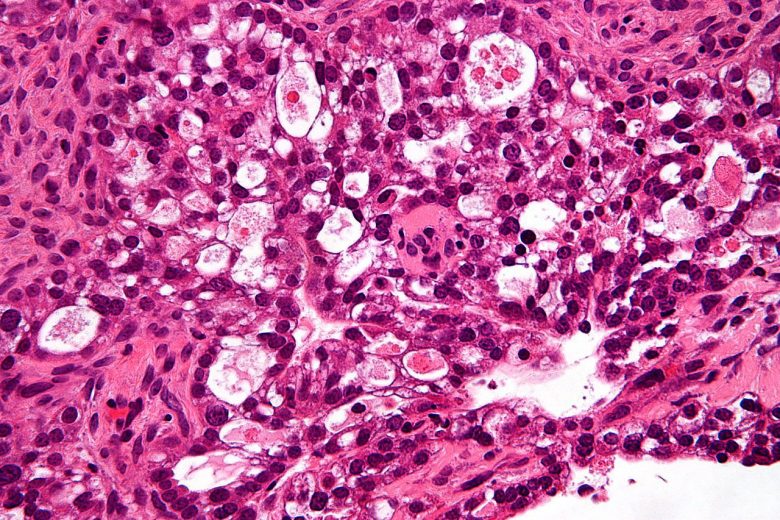

Metastatic cancer

“The main reason that cancer is so serious is its ability to spread in the body. Cancer cells can spread locally by moving into nearby normal tissue. Cancer can also spread regionally, to nearby lymph nodes, tissues, or organs. And it can spread to distant parts of the body. When this happens, it is called metastatic cancer. For many types of cancer, it is also called stage IV (four) cancer. The process by which cancer cells spread to other parts of the body is called metastasis.

“When observed under a microscope and tested in other ways, metastatic cancer cells have features like that of the primary cancer and not like the cells in the place where the cancer is found. This is how doctors can tell that it is cancer that has spread from another part of the body.

“Metastatic cancer has the same name as the primary cancer. For example, breast cancer that spreads to the lung is called metastatic breast cancer, not lung cancer. It is treated as stage IV breast cancer, not as lung cancer.”

Image Credit: Ed Uthman / WIkimedia Commons.